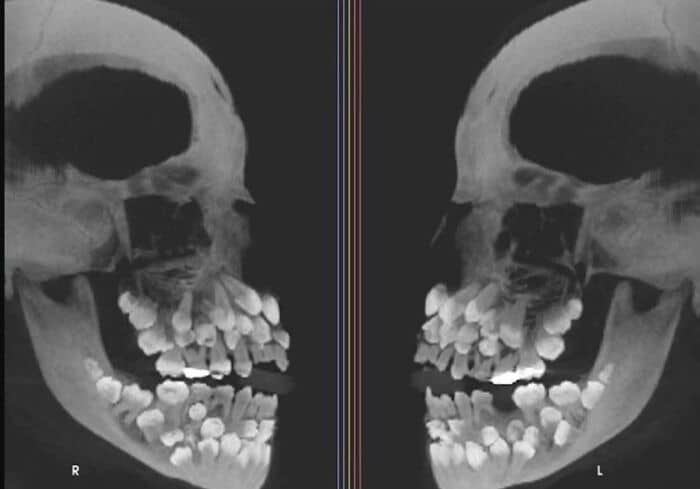

#3 An X-Ray Of A Patient With Hyperdontia (The Condition Of Having More Teeth Than Average). Usually Adults Have 32 Teeth. This Person Had 81